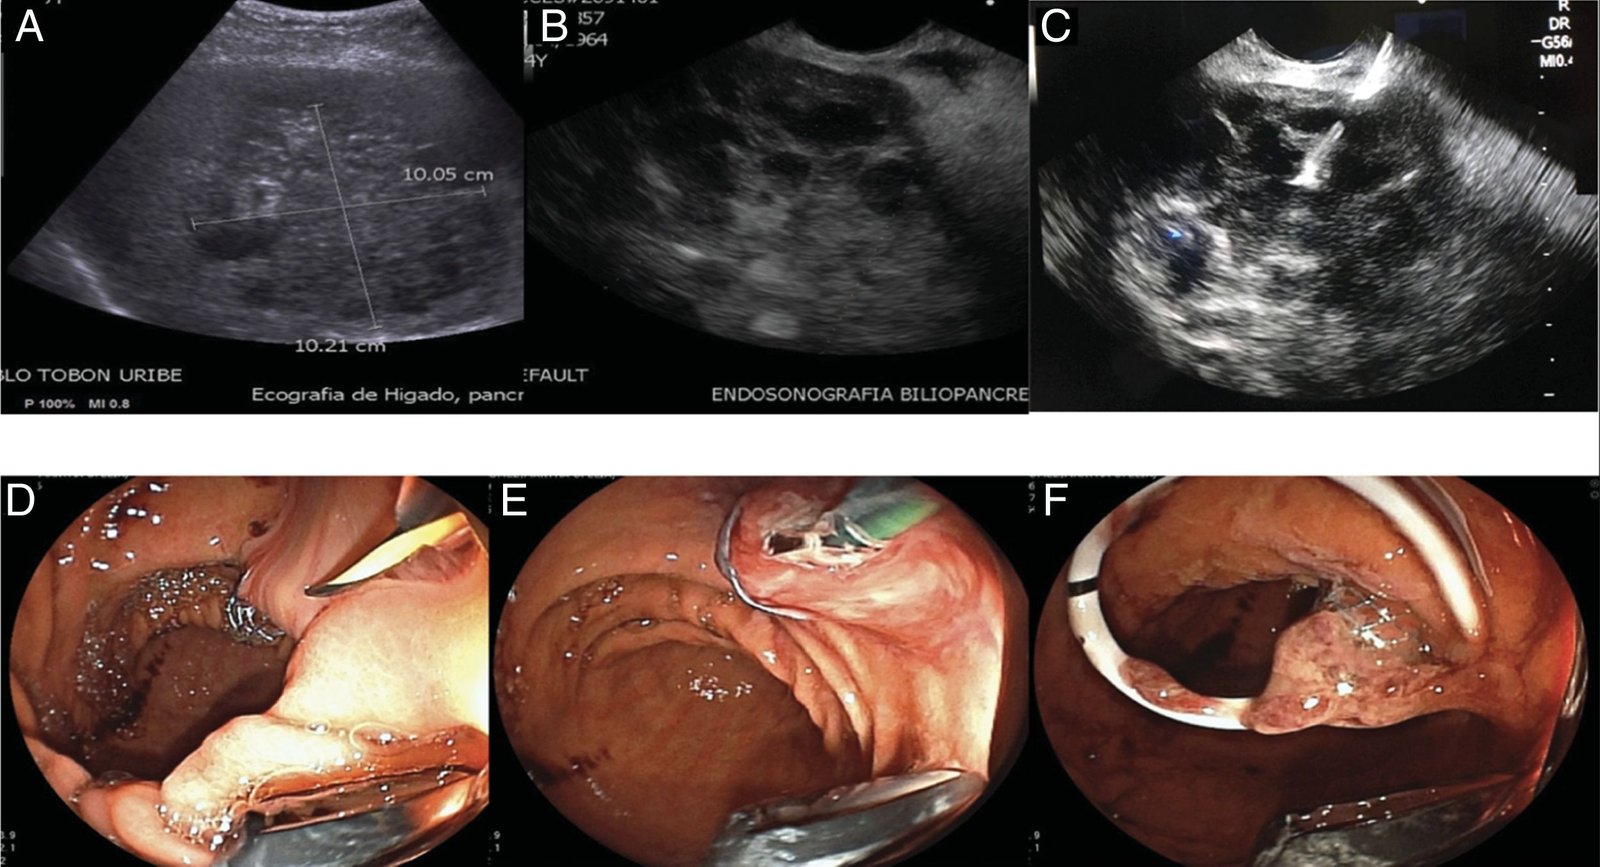

Ultrasound-Guided Pigtail for Liver Abscess

Ultrasound-guided pigtail drainage is a minimally invasive procedure to safely drain liver abscesses, ensuring faster recovery and avoiding the need for open surgery.

Pigtail Catheter Placement